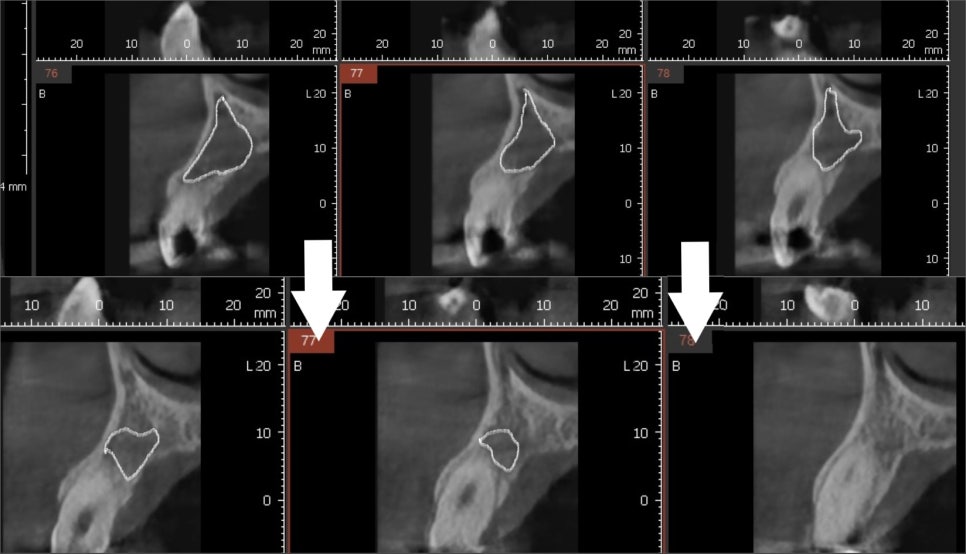

231129 (전) 240215 (후)

놀랍게도 구멍이 뻥 뚫린 것처럼 보였던

염증 부위가

이제는 거의 회복되어 뼈가 단단하게

차오른 것을 확인할 수 있었습니다.

열 번의 소독이 끝난 후

다시 사진을 찍어보았는데요~

까맣게 비어있던 공간이 어떻게 변했을까요?